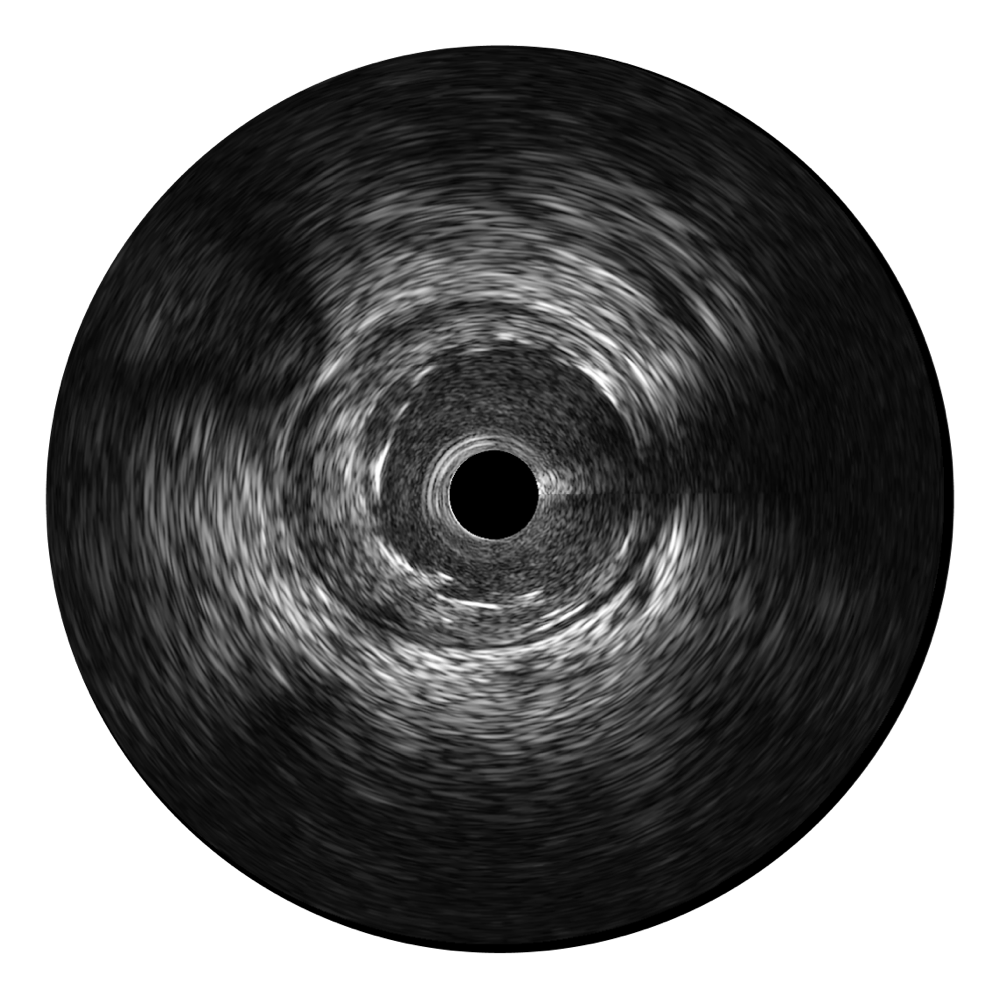

• 竞技宝(JJB)官方网站宽频IVUS图像

对比传统IVUS导管成像,竞技宝(JJB)官方网站宽频IVUS图像的近场支架梁显影更细腻,远场中膜外血管仍清晰可辨,兼顾远中近,兼顾分辨力与穿透深度